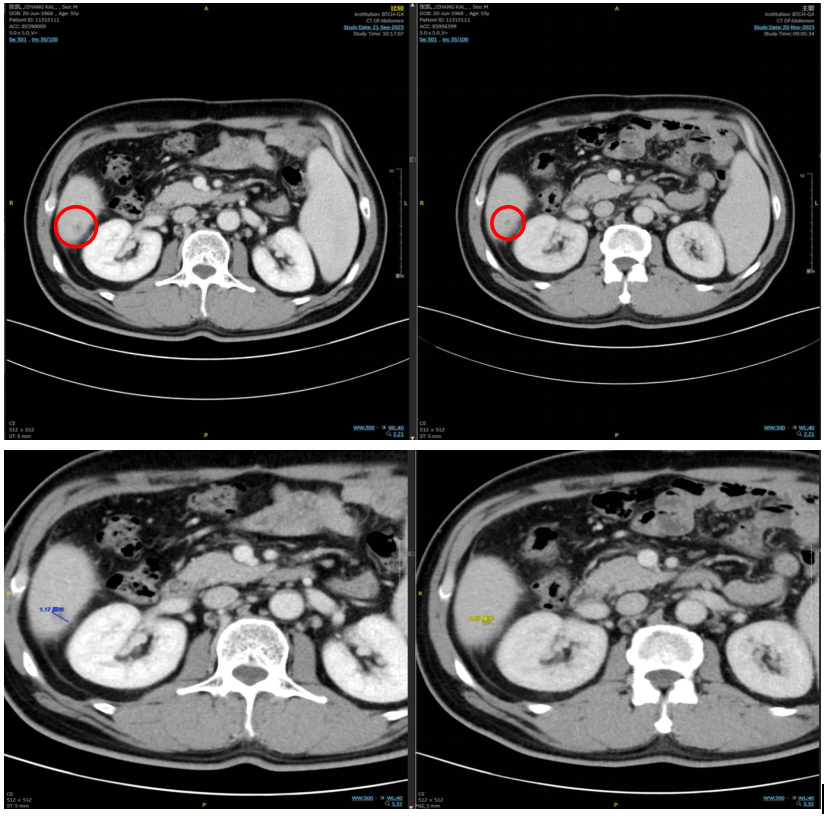

2023年11月23日复查腹部CT,提示靶病灶较前缩小61%,疗效评估PR;

2024年1月15日再次复查腹部CT,提示靶病灶完全消失,疗效评估cCR临床完全缓解;

治疗前后的影像学评估(左上左中(2023-9-22腹部CT)、右上右中(2023-11-23腹部CT)

总体疗效评估:影像学确认的CR(RECIST v1.1),该患者仍在继续治疗中。